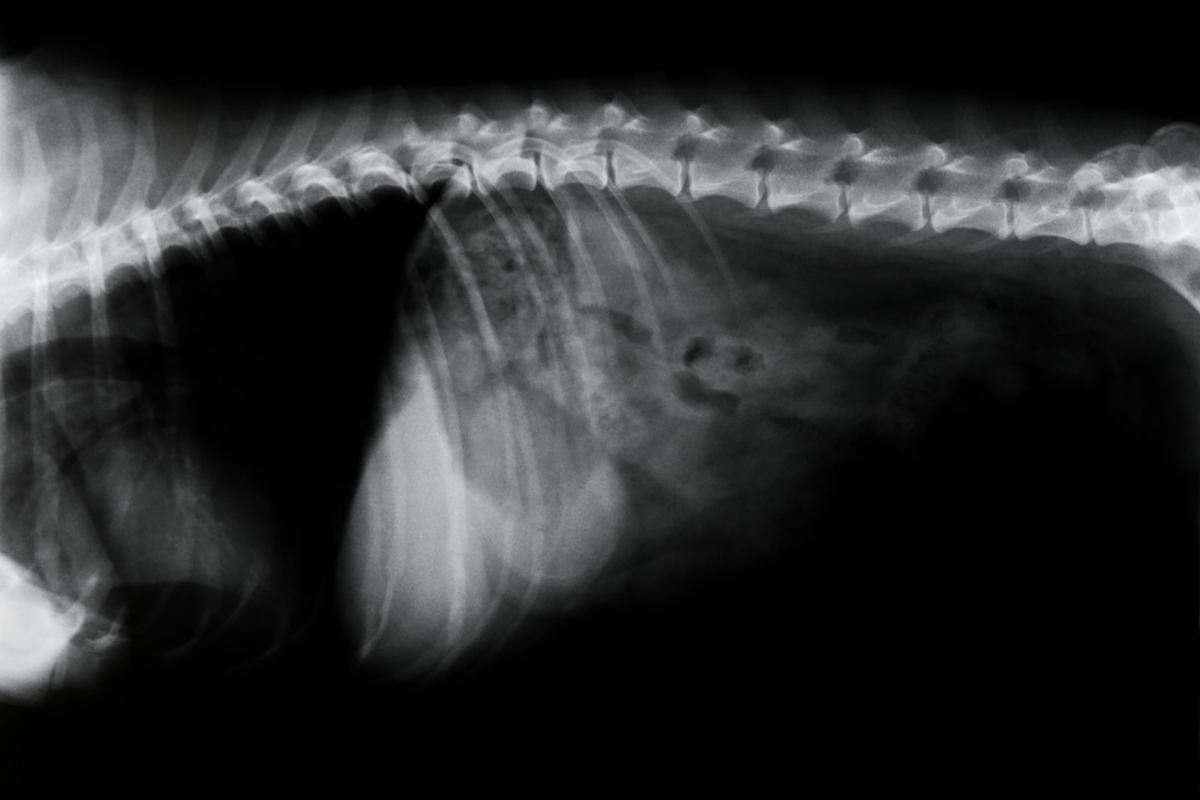

Discopatias

As principais discopatias ou problemas dos discos intervertebrais nos cachorros são a protusão ou a extrusão do material discal dentro do canal vertebral (hérnias discais) ou a degeneração dos discos intervertebrais podendo causar sinais leves incluindo dor de coluna, paresia e ataxia e graves como a paralisia ou a perda da função sensitiva posterior à lesão.

Os discos intervertebrais se encontram entre as vértebras, unindo-as, e rodeados de ligamentos que lhes dão suporte. Possuem uma função de atuar como almofadas intervertebrais para absorver e amortecer as forças de choque, permitir os movimentos e unir as vértebras da coluna para formar um conjunto.

Degeneração discal

A degeneração dos discos invertebrais é mais frequente nas raças que são condrodistróficas como o daschshund, o beagle ou o pequinês, apresentando-se com maior prevalência entre os 3 e os 6 anos de idade. Quando ocorre a degeneração, se perde a elasticidade e pode calcificar.

Dependendo da localização ao longo da coluna vertebral dos cachorros, a sintomatologia terá variações. É muito mais frequente que ocorra na coluna vertebral torácica ou lombar, embora que em 14-16% dos casos pode ocorrer na área cervical produzindo:

As degenerações torácicas e lombares constituem até 86% dos casos e são mais frequentes entre as vértebras torácicas 11 e 12 e na lombar 1 e 2, cursando com sintomas como dor na lombar, incoordenação de movimentos e paresias dos membros pelvianos ou posteriores.